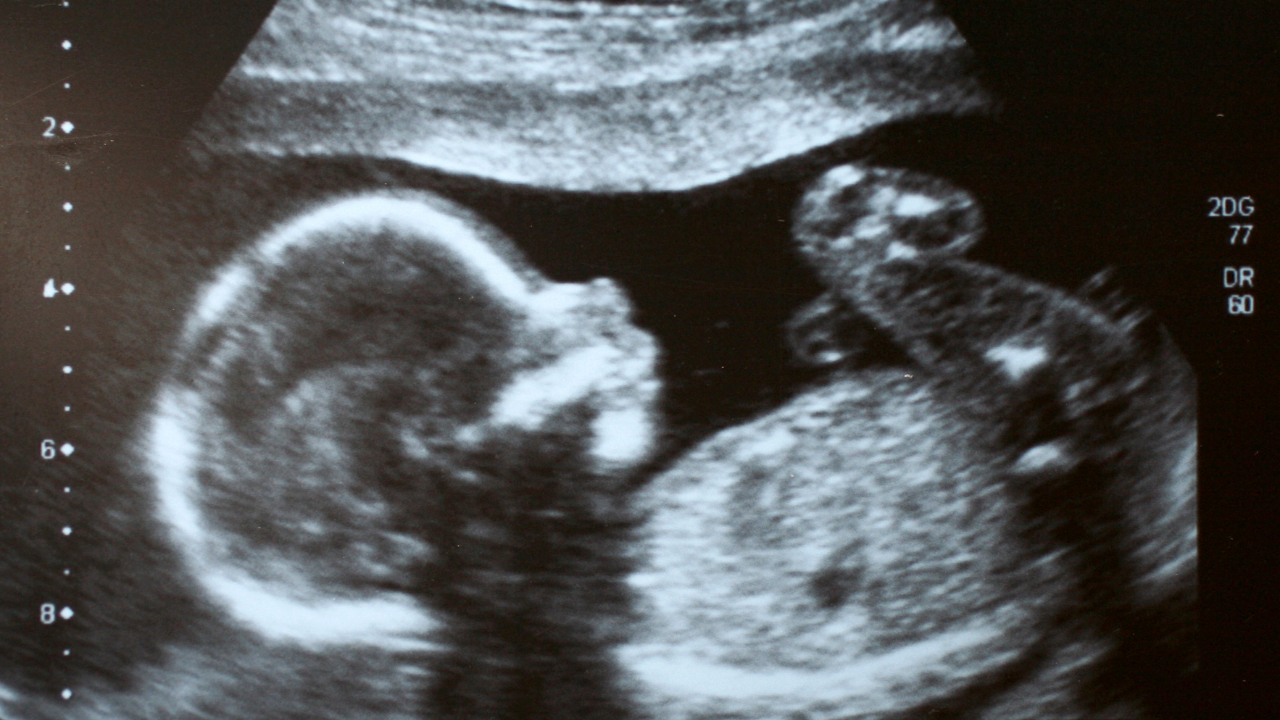

3 tháng giữa thai kỳ (thai 22 - 24 tuần)

Giai đoạn giữa thai kỳ là lúc cấu trúc cơ thể thai nhi đã hình thành rõ ràng. Siêu âm màu 5D lúc này cho phép quan sát chi tiết hình thể bên ngoài và các cơ quan nội tạng của bé. Nhờ hình ảnh rõ nét, bác sĩ có thể phát hiện sớm các dị tật bẩm sinh như sứt môi, hở hàm ếch, bất thường ở tim, não, thận hoặc các cơ quan khác, từ đó có hướng can thiệp và theo dõi kịp thời.